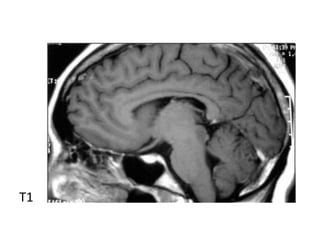

T1